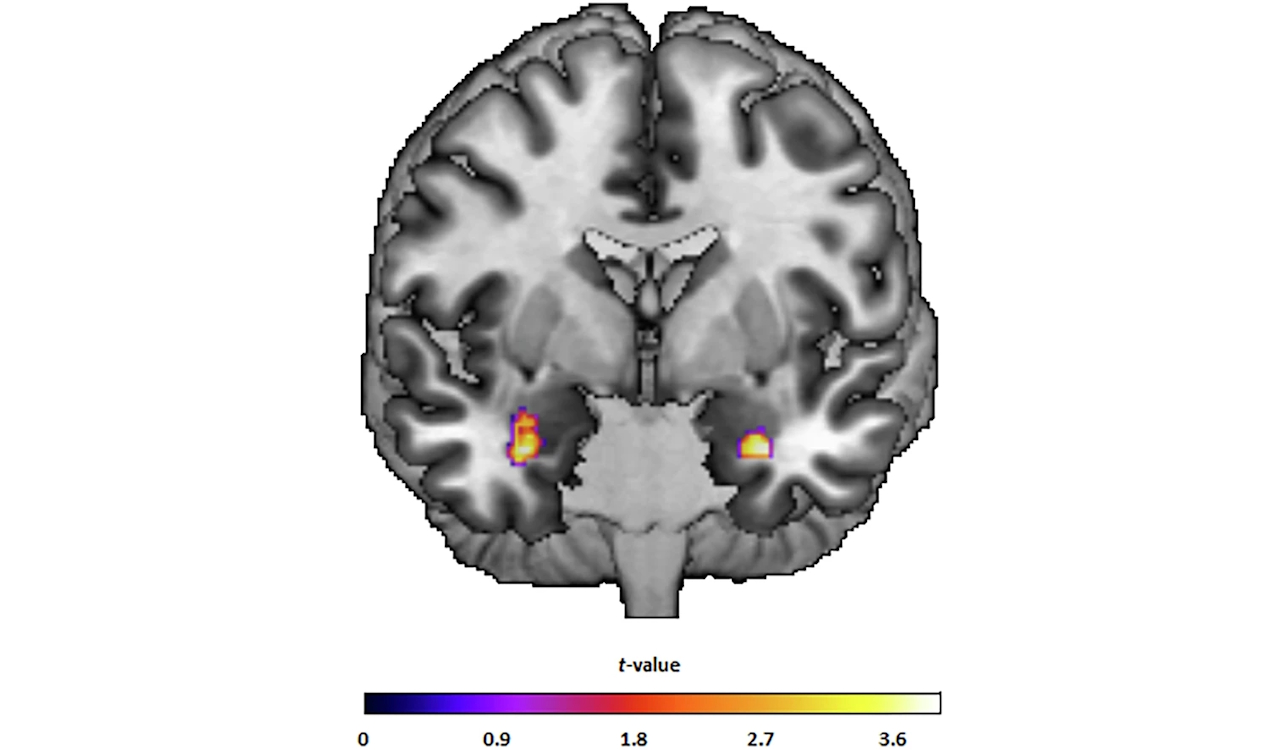

19 з 30 пацієнтів після проходження курсу відчули значне полегшення симптомів: вони перейшли зі стану загострення в часткову чи повну ремісію. В інших пацієнтів також помітили зменшення симптомів депресії. Це супроводжувалося змінами в структурі мозку: порівняно зі здоровими добровольцями, у пацієнтів з депресією помітили збільшення об’єму сірої речовини в мигдалині та передньому гіпокампі, які беруть участь у формуванні та розумінні емоцій, а також — прийнятті рішень.

Зміни об'єму сірої речовини в мигдалині в учасників дослідження. Zwiky et al. / Translational Psychiatry, 2025

Водночас у них зменшився об’єм заднього гіпокампа, який відповідальний за просторову пам’ять. Його зменшення спостерігають у багатьох пацієнтів з великим депресивним розладом і пов’язують із порушенням розумових здібностей. Однак науковці не впевнені, чи зменшення об’єму гіпокампа вказує на нездатність когнітивно-поведінкової терапії побороти вплив депресії на розумові здібності, чи на вікові зміни, які вони не враховували.

У цьому дослідженні науковцям вперше вдалося показати, що зміни в структурі мозку після психотерапії прямо пов’язані з покращенням стану пацієнтів. Ті люди, у яких спостерігали більше зростання об’єму сірої речовини у мигдалині, мали помітніше покращення регулювання емоцій. Це свідчить на користь застосування когнітивно-поведінкової терапії в пацієнтів з депресією.